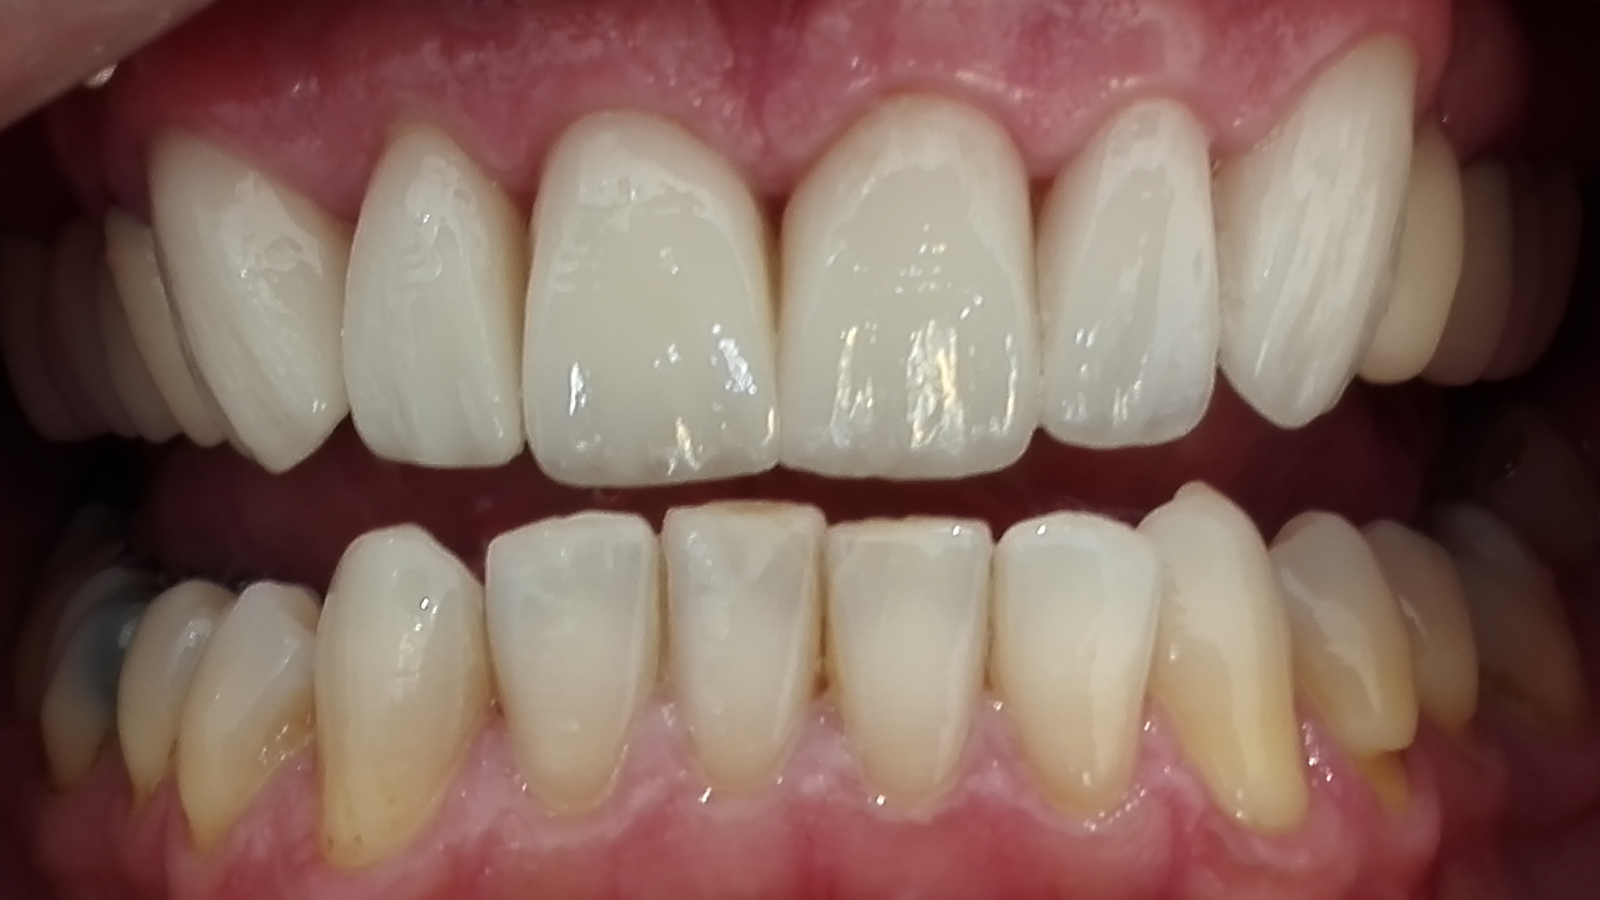

Réhabilitation esthétique après orthodontie : full-zircone & disilicate de lithium

Une jeune patiente arrive en fin de traitement orthodontique pour un déficit esthétique.

La difficulté réside dans la réalisation de prothèses différentes dans le même secteur : jongler avec la full-zircone et le disilicate de lithium.

Ce challenge fut le sujet de mon mémoire du DU d’esthétique de Strasbourg en 2008.

L’expérience et l’investissement dans le digital depuis 2017 rendent le résultat plus prévisible.

Images :